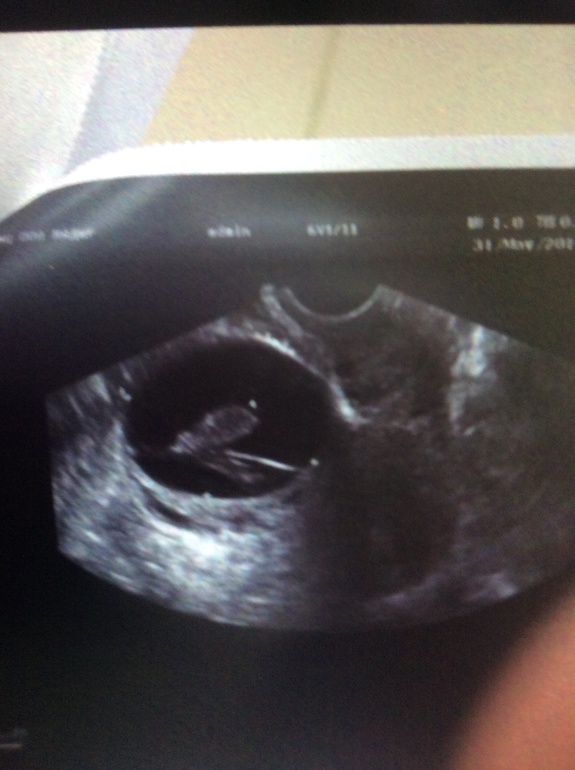

Мама двоих (17 лет, 9 лет)

У меня было 2 недели задержки, оказалась киста , ничего не пила, сама прошла со следущ месячными)причем она была большая , около 5 см. Кстати вот она, сначала поставили 8 недель беременность)))